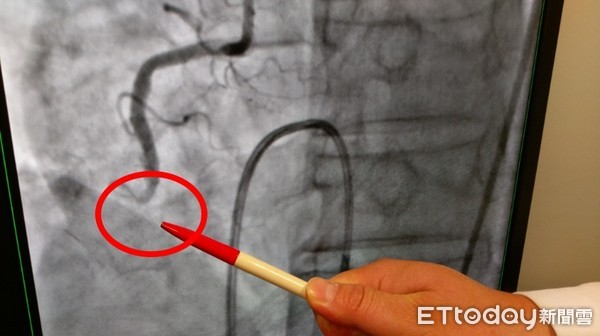

▲陳先生經檢查是下壁急性心肌梗塞。(圖/長安醫院提供)

61歲陳先生平日偶爾會覺得胸口悶悶的、有時有喘不過氣的感覺,但他都不以為意。直到日前和朋友去爬山,爬到半山腰突然喘不過氣,感覺快要昏倒,於是友人趕緊幫他叫救護車,把握黃金12小時送往醫院急診,發現右冠狀動脈下壁急性心肌梗塞,在心導管置放支架,這才救回一命。